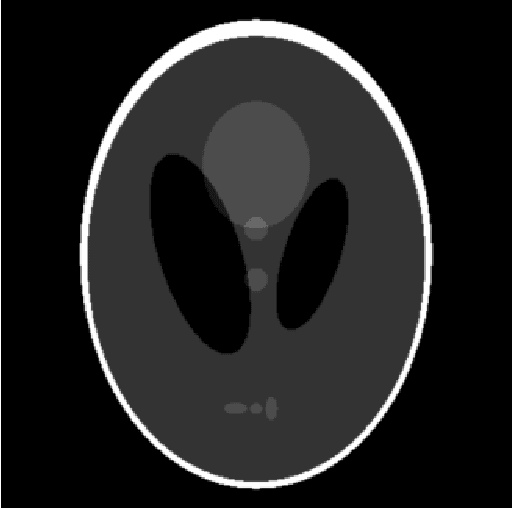

Abstract:This work presents TorchRadon -- an open source CUDA library which contains a set of differentiable routines for solving computed tomography (CT) reconstruction problems. The library is designed to help researchers working on CT problems to combine deep learning and model-based approaches. The package is developed as a PyTorch extension and can be seamlessly integrated into existing deep learning training code. Compared to the existing Astra Toolbox, TorchRadon is up to 125 faster. The operators implemented by TorchRadon allow the computation of gradients using PyTorch backward(), and can therefore be easily inserted inside existing neural networks architectures. Because of its speed and GPU support, TorchRadon can also be effectively used as a fast backend for the implementation of iterative algorithms. This paper presents the main functionalities of the library, compares results with existing libraries and provides examples of usage.